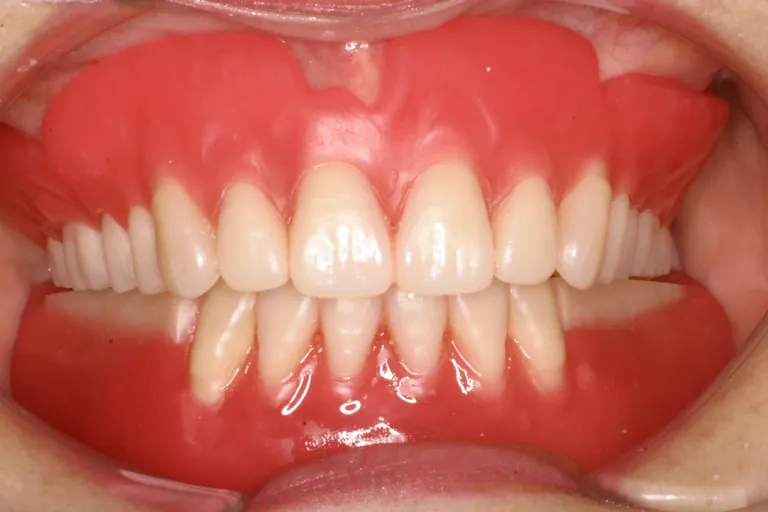

■術後の状態■インプラント・メタルボンド・アタッチメント義歯を含む包括的治療の例です

■術後の状態■

様々な治療法を

用いた

包括的治療の一例

■術後の状態■しっかりと噛める強度と快適な装着感で外からは自然な見た目です

しっかり噛める

口腔環境にします